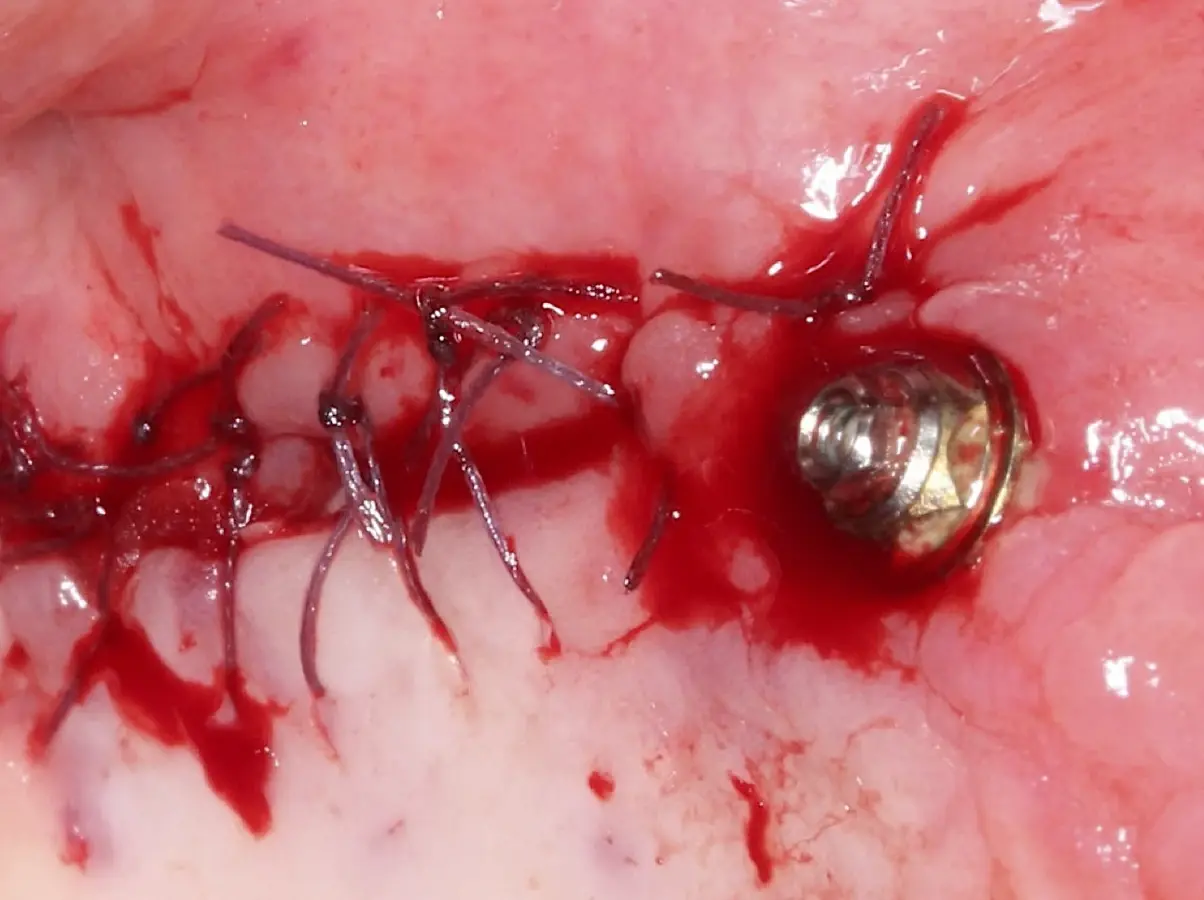

La técnica se inicia con la colocación de anestesia infiltrativa, posteriormente se realiza una incisión crestal o paracrestal con posibles liberantes verticales que deben de estar alejadas por lo menos 5 mm de los límites de la futura ventana y sobrepasar la línea mucogingival. Se realiza una elevación de colgajo, se inicia la antrostomía y antroplastía. Para ello, se emplea el inserto redondo diamantado de corte al momento de delimitar los bordes de la ventana de acceso. Luego se cambia al inserto aserrado liso de calibre fino con superficie diamantada, para profundizar y eliminar el hueso en el contorno de la ventana. Una vez que se traslucen los tejidos, se puede optar por el retiro de la tapa ósea o el levantamiento de ésta junto con la membrana.

Se inicia la elevación de la membrana de Schneider con el inserto redondeado no cortante en forma de disco, empleando movimientos suaves. El levantamiento puede complementarse con elevadores convencionales, siguiendo la dirección mesiodistal. La fase de desprendimiento inicia con el piso y sigue hacia la pared mesial para terminar, y de ser necesario, hacia la pared posterior. Existen diversos insertos con angulaciones y longitudes para mayor accesibilidad16 (Figura 1).

Una vez elevado el piso sinusal según la planificación se realiza la evaluación clínica de la integridad de la membrana y de posibles desgarros a través de la maniobra de Valsalva.24 Consiste en pedir al paciente que respire profundamente y retenga el aire, cerrar la boca, apretar la nariz con los dedos y forzar la salida de aire. Al final de la prueba, es necesario mantener la presión entre 10 a 15 segundos. Se identificará la movilidad de la membrana y la ausencia de burbujas de aire para corroborar que no hay perforaciones. Dependiendo de la decisión clínica se puede optar por adicionar en la superficie de la membrana de Schneider membranas de colágeno o de plasma rico en fibrina (PRF) para dar mayor soporte durante la inserción del biomaterial de relleno óseo (Figura 10).